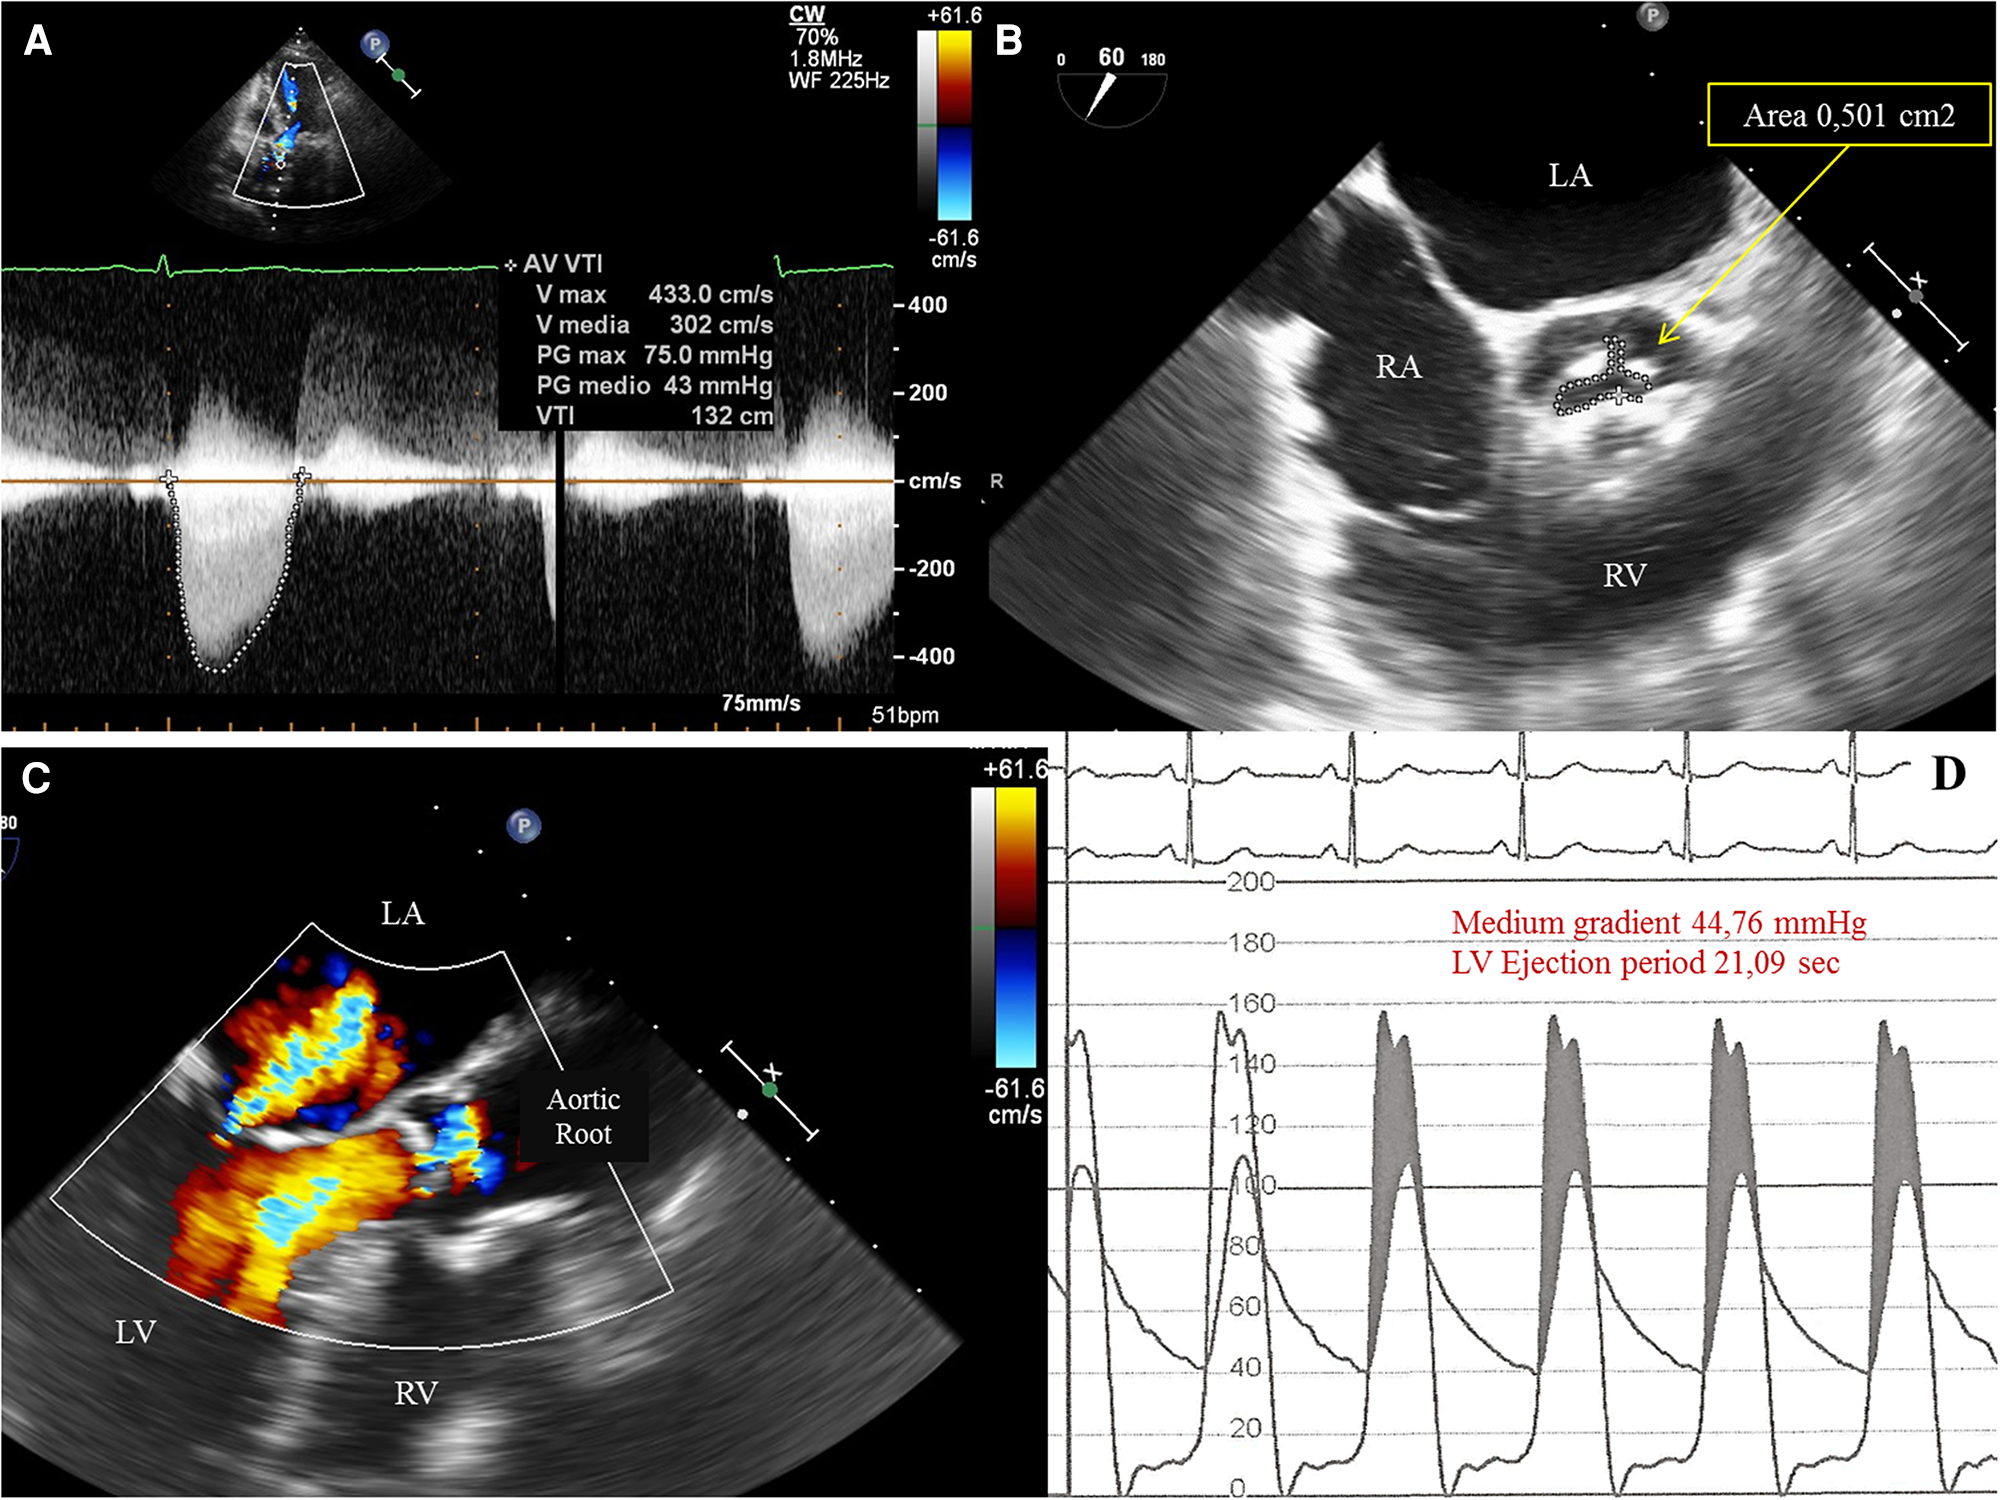

Figure 1

(A) Transthoracic echocardiography (TTE) 5-chamber view showing increased peak and medium transvalvular aortic pressure gradient of, respectively, 75 mmHg and 43 mmHg. (B)Transesophageal echocardiography (TEE) showing a tricuspid aortic valve with severe stenosis and a planimetric aortic valve area of 0,5 cm2. LA, left atrium; RA, right atrium; RV, right ventricle. (C) TEE showing a mild mitral valvular insufficiency with neither significant subvalvular and/or intraventricular pressure gradient nor evidence of systolic anterior motion (SAM) of the anterior leaflet of the mitral valve. (D) Invasive simultaneous registration of left ventricular (LV) and aortic pressures showing a significant transvalvular pressure gradient during the ventricular ejection period. LV pressure exceeds the aortic pressure (gray area, pressure gradient generated by valvular stenosis). The LV peak systolic pressure during ejection ranged between 152 to 156 mmHg and the aortic pressure between 102 to 106 mmHg. No elevated LV telediastolic pressure was documented.).